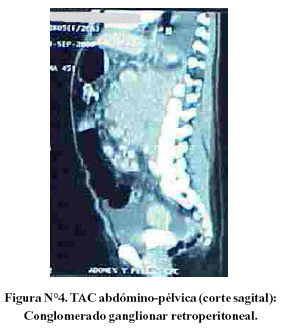

La TAC de tórax reveló solo derrame pleural bilateral y atelectasia pasiva adyacente. La TAC abdómino-pélvica mostró conglomerados ganglionares retrocrurales y paraaórticos que se extendían hacia adelante y englobaban el tronco celíaco, vasos mesentéricos y arterias iliacas primitivas. Ascitis marcada. El resto sin mayores alteraciones (Figura N°2, Figura N°3 y Figura N°4).